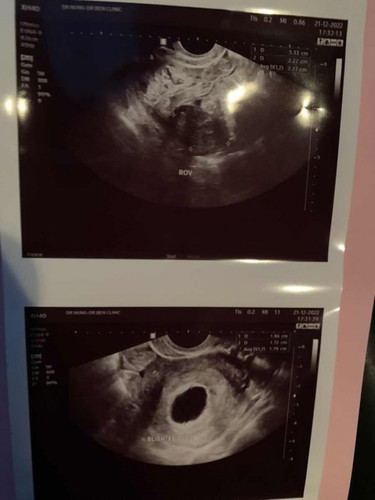

ซาวด์ครั้งแรก5ธค ไม่เจออะไร ซาวด์ครั้งที่2 วันที่21ธค เจอแค่ถุงตั้งครรภ์ ขนาด4ซม .หมอแจ้งว่าท้องลม ให้ยุติการตั้งครรภ์ เราเครียดมากค่ะ ควรทำยังไงดีคะ ควรรอดูอีกซัก2weeks มั้ยคะ ประจำเดือนเรา45-60วันมาครั้งค่ะ แล้วแต่รอบ #คุณแม่ๆช่วยแนะนำหน่อยค่ะ